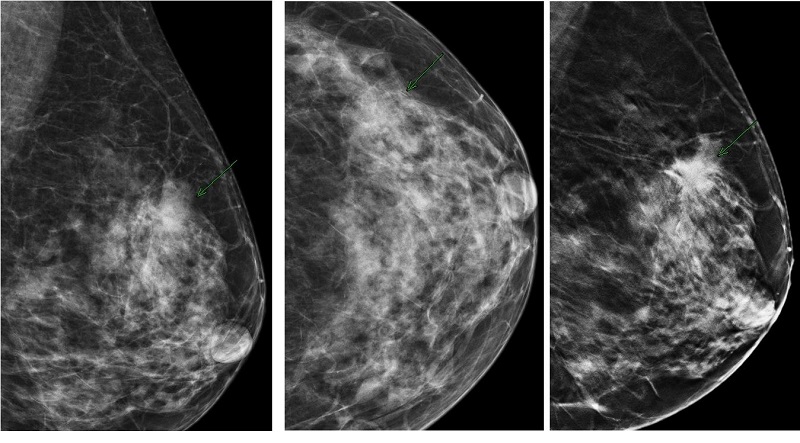

Chụp X Quang Tuyến Vú: Những Điều Bạn Cần Biết

Chụp X quang tuyến vú là một trong những phương pháp tiêu biểu để tầm soát ung thư vú sớm. Kỹ thuật này có nhiều ưu điểm giúp bác sĩ chẩn đoán...